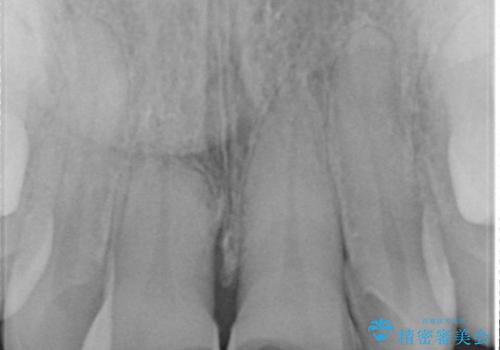

- 白い詰め物が急に外れたとの事で来院された患者様です。前歯にデンタルフロスも出来ず気になっていたとの事でした。

神経の検査をした所、問題ないので神経を残して被せ物の処置を行いました。